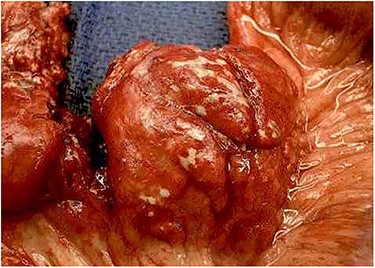

A large necrotic mesenteric lymph node with a ruptured capsule showing purulent drainage.

Emergent laparotomy was performed. He was found to have multiple enlarged necrotic mesenteric lymph nodes with purulent material draining from the capsule of the nodes (Fig. 2). Several large areas of the proximal mesenteric fat were necrotic with vascular occlusion and thrombosis, which was causing ischemia of the proximal jejunum. The proximal jejunum was very dusky and dilated, while the distal small bowel and colon was normal. The duodenum was spared. The necrotic fat and lymph nodes extended down to and around the superior mesenteric artery, where multiple side branches off the artery showed no blood flow by Doppler examination. The ischemic small bowel was excised along with its mesentery down to the superior mesenteric artery, to include the excision of the necrotic lymph nodes (Fig. 3). The bowel was left in discontinuity, and the patient was taken to the intensive care unit with a temporary abdominal closure. He was taken back to the operating theatre the next day for a second look, and the remaining small bowel was found to be viable and healthy. A duodenal to distal jejunal anastomosis was performed and the abdomen was closed.